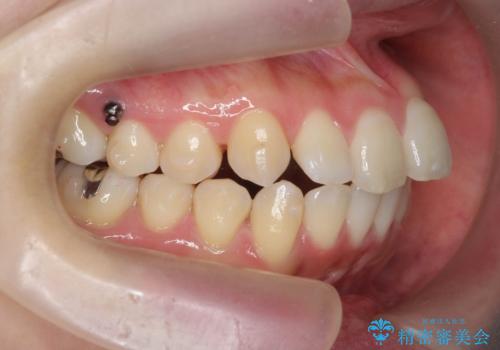

上下の歯は、上顎の歯が相対的に前に位置する咬合関係で押し出されるように前歯に角度がついている状態です。

咬合関係の改善、前歯の角度、がたつきを改善するため、マイクロインプラントを用いて上顎の奥歯を後方へ移動させていきます。